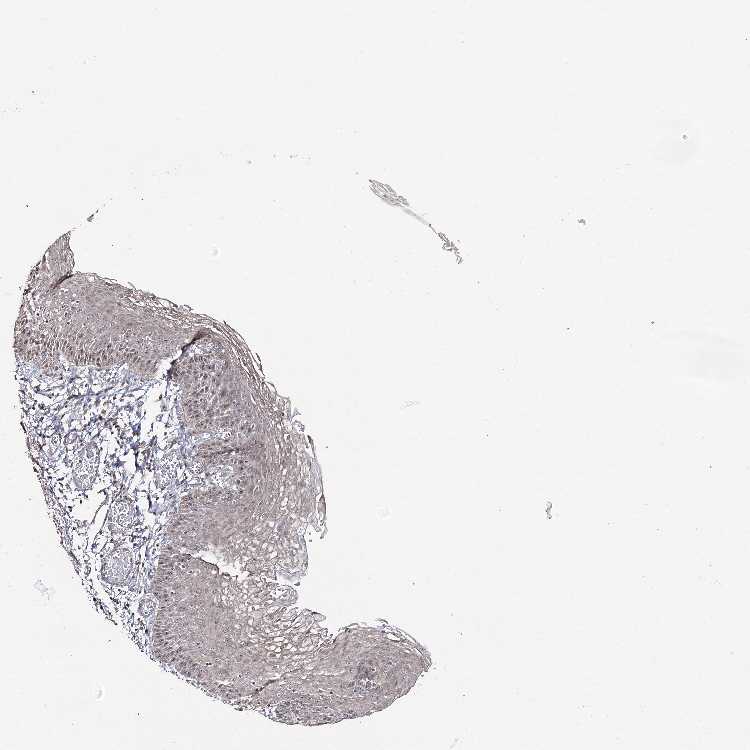

ESOPHAGUS - Antibody stainingi

Antibody staining in the annotated cell types in the current human tissue is reported as not detected, low, medium, or high, based on conventional immunohistochemistry profiling in selected tissues. This score is based on the combination of the staining intensity and fraction of stained cells.

Each image is clickable and will lead to virtual microscopy that enables deeper exploration of all samples and also displays staining intensity scores, fraction scores and subcellular localization as well as patient and tissue information for each sample.

Antibody HPA037980

Squamous epithelial cells Medium